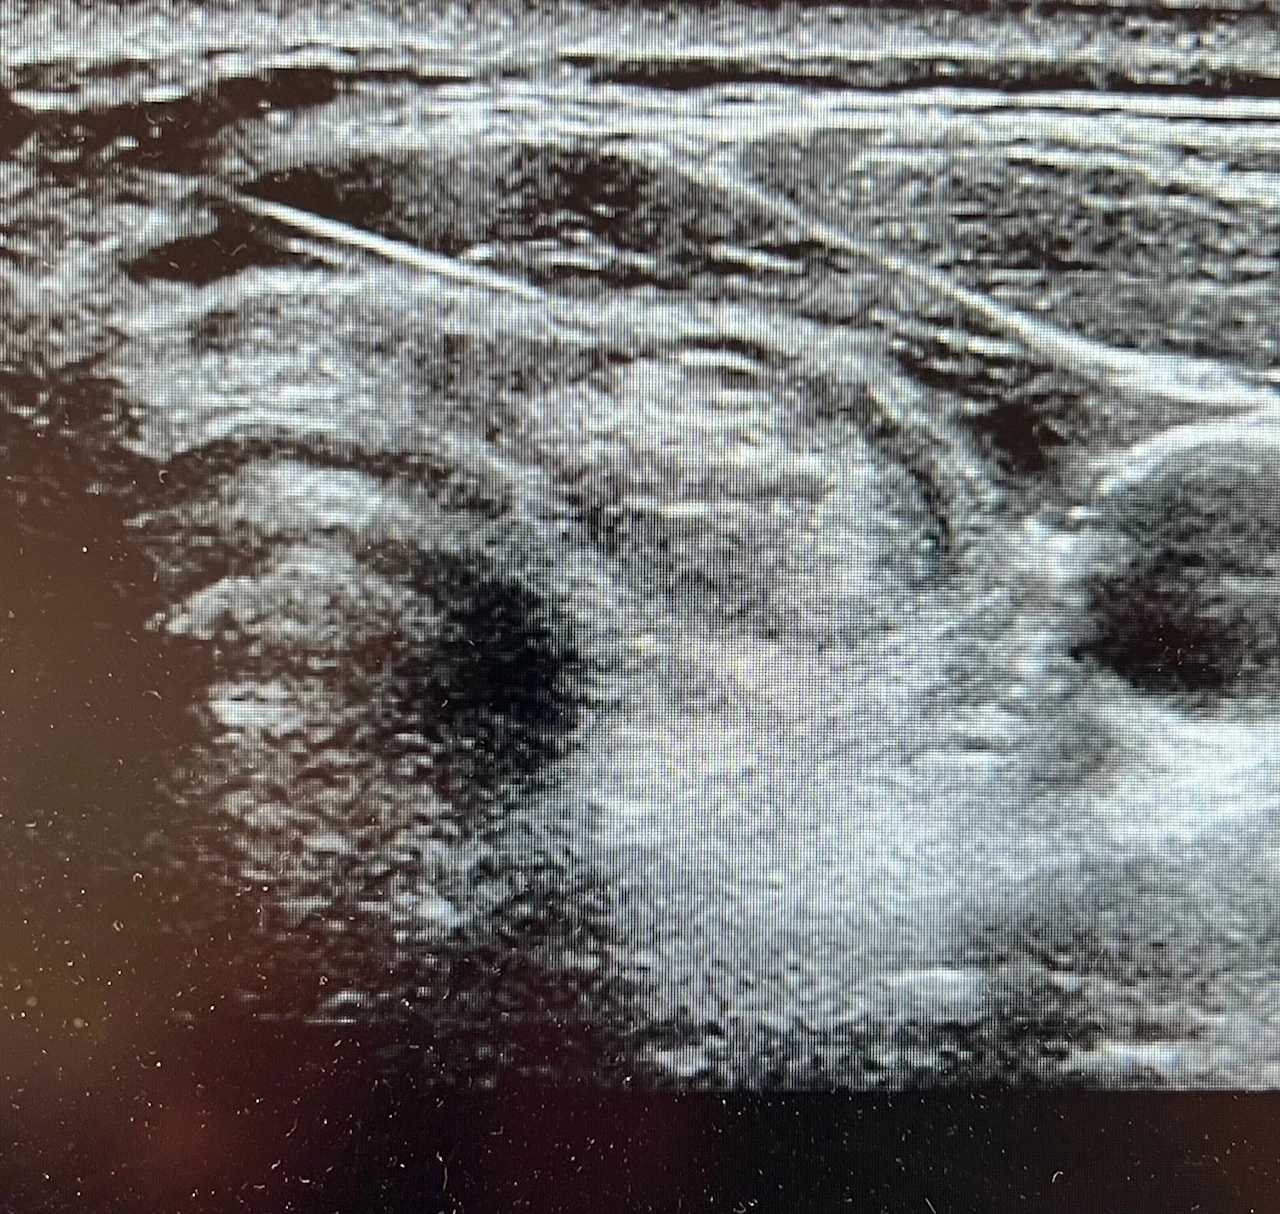

🎓 Très heureux d’annoncer la validation de mon diplôme d’échographie thyroïdienne.

Un complément indispensable à la spécialisation en chirurgie thyroïdienne, qui renforce l’autonomie du chirurgien dans le diagnostic, la cytoponction, l’alcoolisation et la thermoablation.